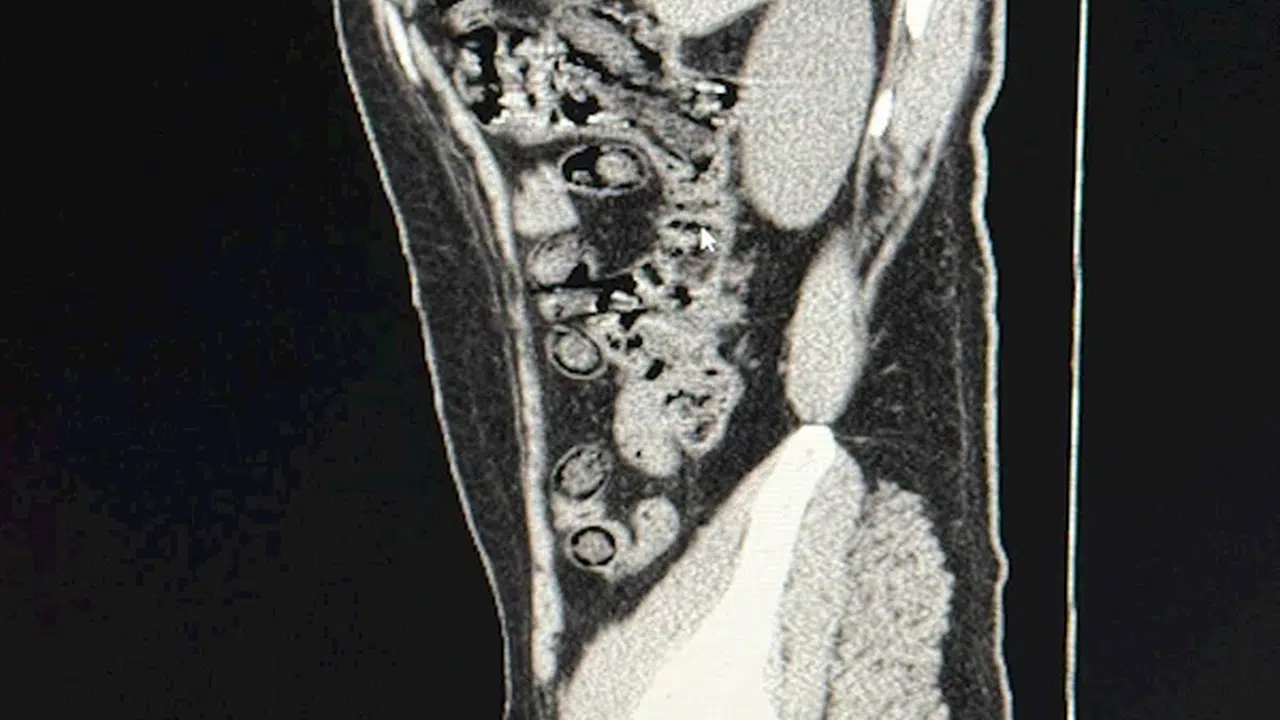

Muhammed Sami MARAL/ MUŞ, (DHA)- MUŞ’ta İran uyruklu 2 kişinin midelerinden 94 adet kapsül halinde 928 gram metamfetamin maddesi çıkarıldı.

Muş Emniyet Müdürlüğü Narkotik Suçlarla Mücadele Şubesi ekipleri, uyuşturucu madde nakli gerçekleştirdiklerinden şüphelendikleri İran uyruklu 2 kişiyi gözaltına aldı. Yapılan sorgulama sırasında davranışlarından şüphelenilen İranlı 2 kişi, hastaneye götürüldü. Burada çekilen tomografi sonucu şüphelilerin uyuşturucu madde yuttukları belirlendi. Hastanede yapılan müdahale ile 2 şüphelinin midesinden 94 adet kapsül halinde toplam ağırlığı 928 gram metamfetamin çıkarıldı. İşlemlerinin ardından adliyeye sevk edilen şüpheliler, nöbetçi sulh ceza hakimliği tarafından ‘uyuşturucu ve uyarıcı madde ticareti’ suçundan tutuklandı.